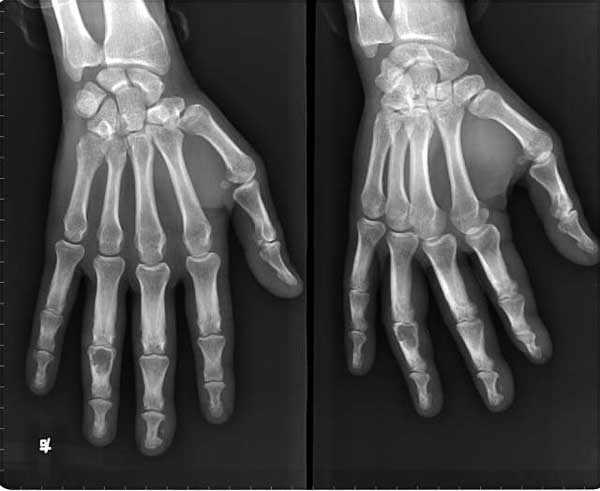

以下是引用ctm在2005-4-19 18:28:02的发言:[br]发生于手指指骨,膨胀性生长,囊状低密度影,其中沙砾样钙化。骨皮质变薄硬化。典型内生骨软骨瘤。

以下是引用枫叶在2005-4-21 0:03:53的发言:[br][br] \"支持血管球瘤\"______不知真人怎就这样想了???[br]我还是支持\"典型\"的内生软骨瘤!!! [br] [br]